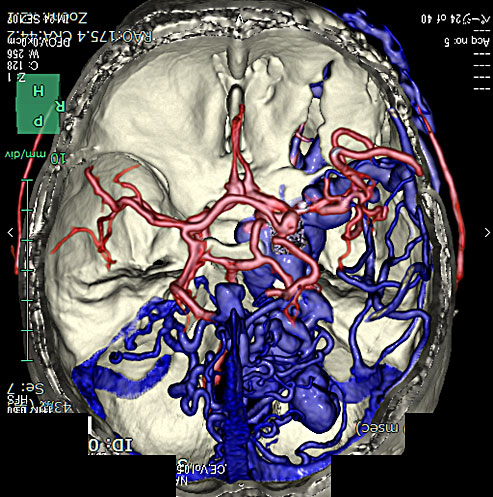

1) 脳血管撮影

3) 頭部CT、CTA

4) 頭部MRI、MRA